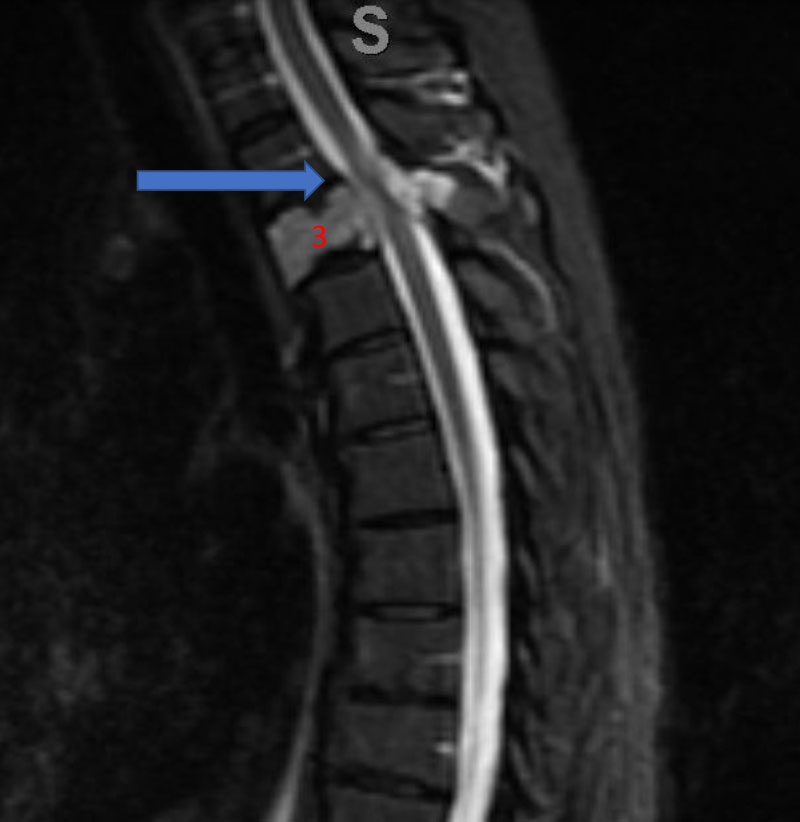

He presented to the emergency room with a one-week history of thoracic pain in addition to bilateral lower extremity weakness and paraparesis. MRI imaging with contrast showed a diffuse abnormal signal within the vertebral body of T3 and the posterior elements with lobulated soft tissue lesion extension into both paraspinal areas (Figure 1. A, B, C).

Figure 1. A) Sagittal T2 MRI demonstrates aggressive hyperintense T3 hemangioma involving the body and posterior elements compressing the thoracic spinal cord (arrows)

Figure 1. B and C) Axial MRI images of T3 demonstrates extensive infiltrative lesion with extradural compression of the thoracic spinal cord. (Dashed lines in A) tumor infiltration; Dashed lines and Arrows in B) cord compression.

Significant spinal cord compression was identified with no other bony lesions in the entire spinal axis. Metastatic work-up was also negative. A diagnosis of vertebral body hemangioma, an aggressive subtype, was made and spinal surgery consultation obtained. Our neurosurgical team was consulted for preoperative embolization of the tumor prior to surgical decompression and instrumented fusion.